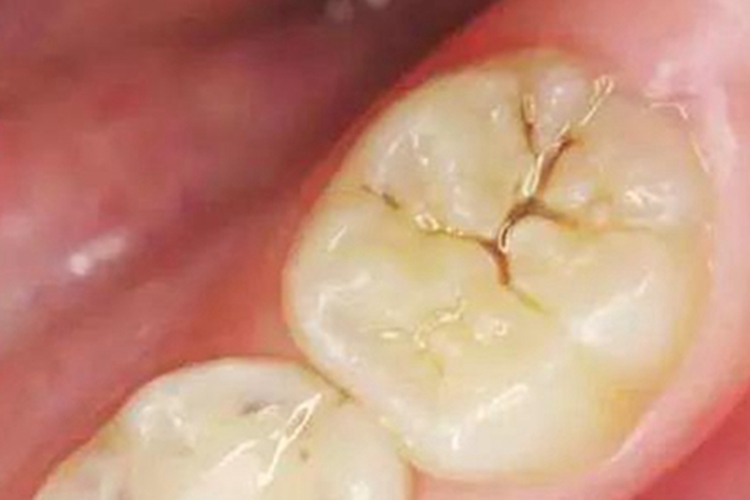

浅龋患者可见在牙齿上出现细小的树枝样裂痕,常呈黄褐色。本病可由不注意口腔卫生,食物残留或细菌生长所致,可遵医嘱进行治疗。

浅龋患者可见在牙齿上出现细小的树枝样裂痕,常呈黄褐色,吃刺激性食物时,患牙常无疼痛症状。若不及时治疗,病损处会逐渐扩大。

浅龋可导致牙齿表面断裂,如不注意口腔卫生,可导致食物残留或细菌生长,引起裂缝颜色变深,呈褐色。